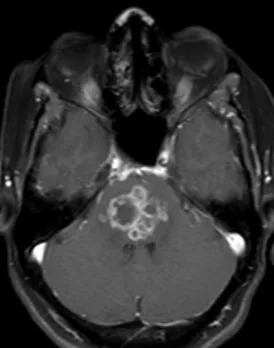

- Mechanism: Paramagnetic agent. Shortens the T1 relaxation time of nearby water protons, leading to a brighter signal (T1 hyperintensity) in tissues where it accumulates.

- Detecting and characterizing tumors, inflammation, and infections.

- Assessing blood-brain barrier integrity.